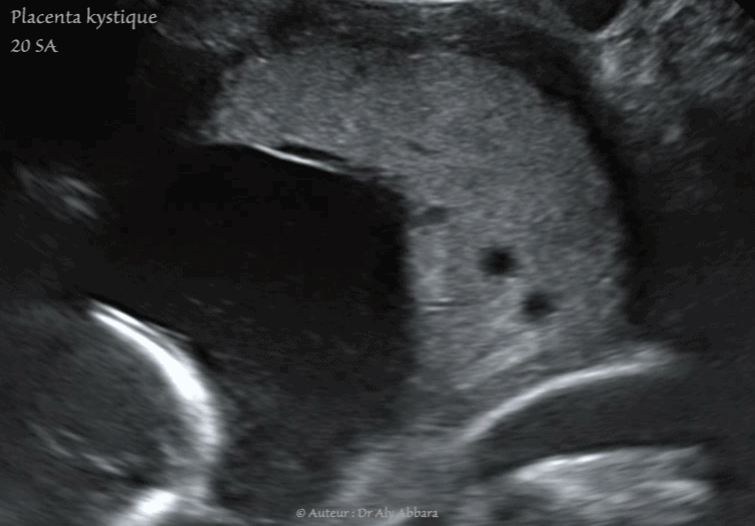

Placenta Kystique Kystes Placentaires Intra Parenchymateux Cytotrophoblastiques Sa